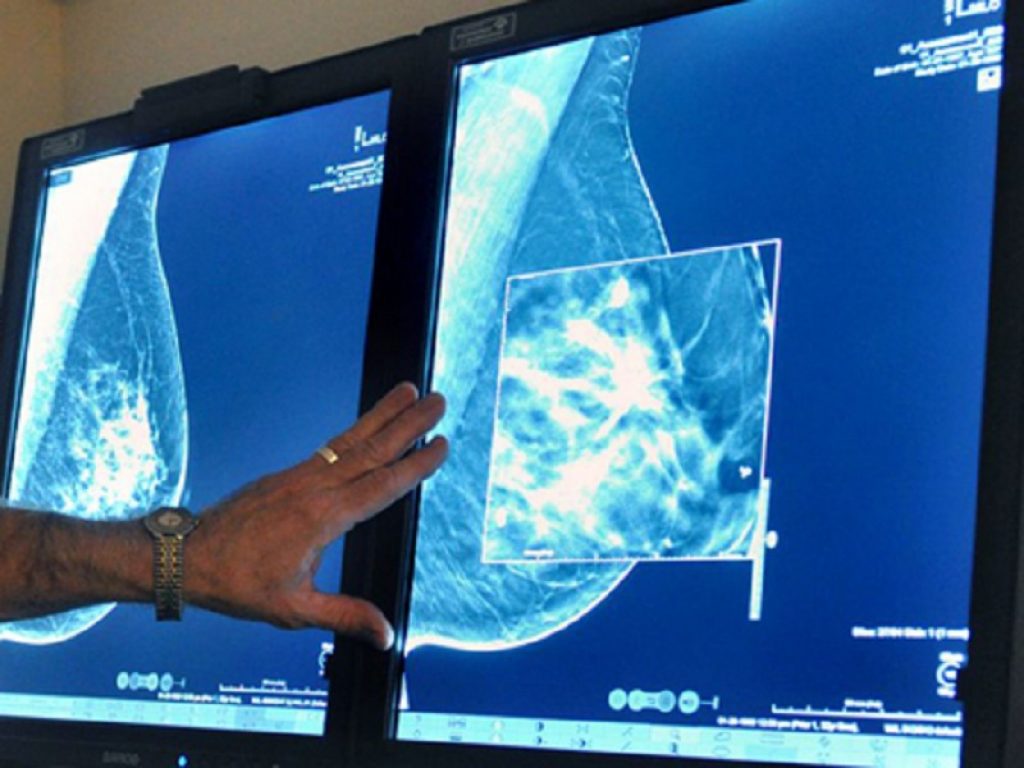

Tumore al seno metastatico, abemaciclib rimborsato in Italia. Si usa in associazione con un NSAI e senza la chemioterapia

Abemaciclib, approvato e rimborsato dall’AIFA lo scorso 12 dicembre, è disponibile anche sul mercato italiano per tutte le pazienti, in pre, peri e post-menopausa, con carcinoma mammario avanzato o metastatico positivo ai recettori ormonali (HR+), negativo al recettore del fattore umano di crescita epidermico di tipo 2 (HER2-). Si parla dunque del tipo di tumore del seno più frequente, che riguarda circa il 70% del totale dei casi in stadio avanzato. La somministrazione è prevista in associazione con un inibitore dell’aromatasi non steroideo (NSAI; anastrozolo o letrozolo) o fulvestrant; o come terapia endocrina iniziale o in donne che hanno ricevuto una precedente terapia endocrina.